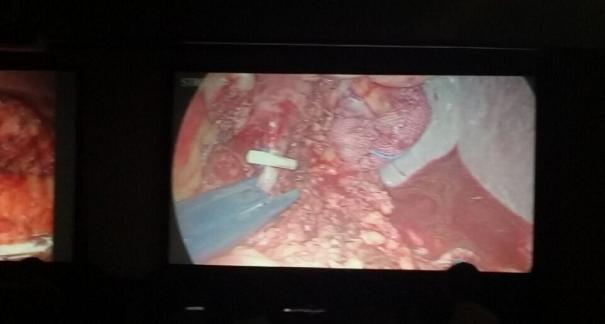

2015年10月23-25日,河北省醫學會肝膽外科學術年會在河北省石家莊市頤園賓館隆重召開。本次學術會議河北省醫學會特邀了北京301總院的胡明根教授、天津第一中心醫院的張雅敏教授、山西醫大醫院的趙浩亮、河北醫科大學第二醫院劉建華教授等國內知名專家參會。參加會議的醫院達100余家,近300名肝膽外科的臨床專家和一線醫生們親臨會場,在此進行廣泛的學術交流。25號全天會議安排了五臺手術視頻演示,全體參會人員進行觀摩,并實時提問,進行手術交流。演示手術包括腹腔鏡胰、十二指腸切除術、腹腔鏡左、右半肝切除術、腹腔鏡門脈高壓癥的治療、兩鏡或三鏡聯合膽石癥的治療、開腹胰、十二指腸切除術、手術演示中多次使用了我公司產品速豐(可吸收止血結扎夾),產品使用滿意度受到專家們的一致好評。